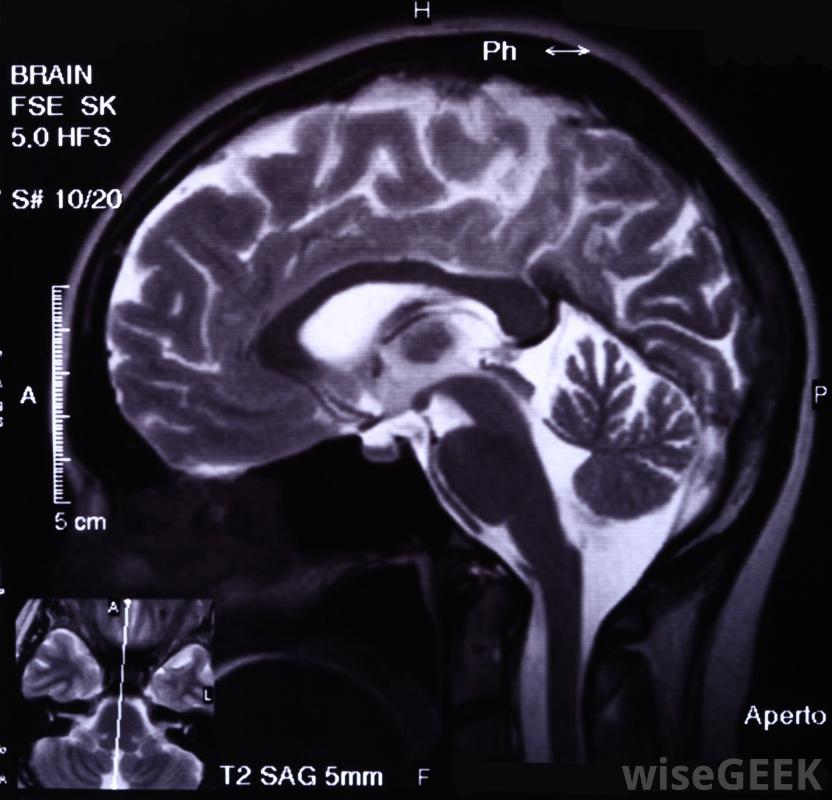

腫瘤進展是指癌性腫瘤在生長或擴散過程中經過的步驟和階段,單個腫瘤的發展通常包括三個階段:增生、異型增生和癌癥。隨著癌癥轉移到其他階段,惡性腫瘤的整體癌癥進展也可能經歷四個或更多個獨立的階段一些基因的突變通常會為腫瘤的發展創造條件生長促進單個腫瘤的進展,單個細胞的改變為增生奠定了基礎。起源細胞的遺傳改變的原因常常是未知的。當這些細胞開始發生結構變化時,這些細胞已經達到了發育不全的階段,當它們開始發生結構變化時,就會出現異常和不規則的外觀。一旦這些細胞覆蓋了一個很大的容納區域,并屈服于使它們無法發揮其原有功能的功能時,癌細胞就發生了MRIs和其他成像掃描可用于定位和測量腫瘤原位癌代表一個單一的腫瘤。由于細胞的無序性,腫瘤通常表現為堅硬、致密的腫塊。它們幾乎可以發生在人體的任何細胞中,因此腫瘤可以在任何器官上發現發生在血液或皮膚上的癌癥可能呈現不同或不明顯的異常外觀。任何惡性腫瘤都可能開始轉移。單個腫瘤的發展通常包括三期:增生、異型增生和癌癥。轉移促進腫瘤向其他階段發展,身體以前不受影響的區域。兩種基因的突變通常為腫瘤的進展創造條件:癌基因和抑癌基因。癌基因是體內負責細胞分裂和細胞運動的物質。有時,這些基因的改變會導致它們過度發揮影響,同時,突變可能使腫瘤抑制基因失活,這些基因是阻止細胞異常分裂的安全衛士;如果它們被中和,癌基因就會毫無節制地進行破壞性行為惡性腫瘤可引起體溫升高。癌癥的進展通常分為幾個階段,這些階段的特征是最初的腫瘤促進或進展以及轉移的程度除了上述細胞的構成和擴散的表現外,決定癌癥分期的其他因素包括腫瘤大小、腫瘤位置和淋巴結在癌癥中的特殊作用,但是有一個眾所周知的系統將癌癥和腫瘤的發展分為四個階段,較晚期的三期或四期癌癥通常包括較大的腫瘤和已經到達淋巴結的腫瘤細胞,在最嚴重的晚期癌癥中,也會發生周圍器官的轉移惡性腫瘤可以用化療治療。